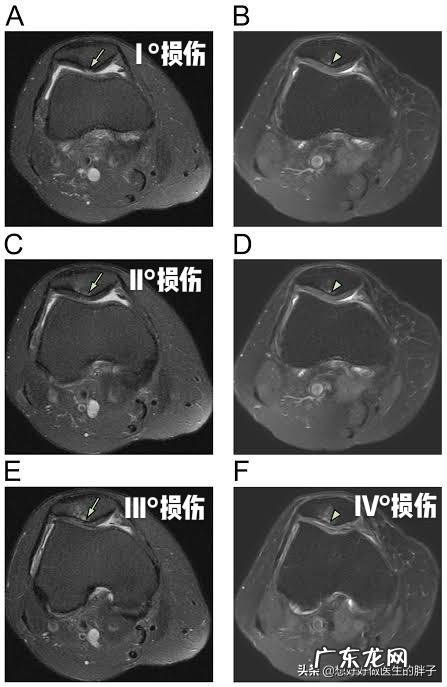

diyi,半月板撕裂 。我们膝关节内有两块非常重要的软骨,因为形状像月牙,所以称之为半月板 。半月板其实就是两块比较大的软骨,在关节的屈伸活动当中,它的形态是动态变化的,会有厚薄的变化以及宽窄的变化,这样才能更好的缓冲关节在运动当中承受的压力,匹配关节的形状,使关节能够做正常的屈伸运动 。